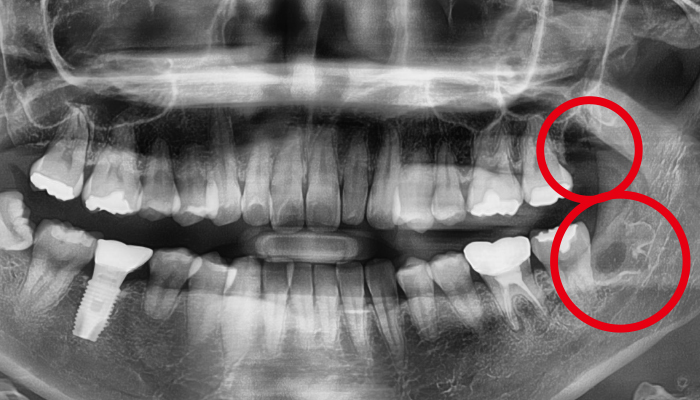

사랑니 발치 전후 사례

• 치료전

치료후